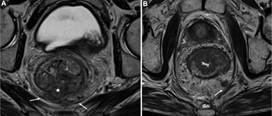

Estadificación N

El estadio N está determinado por la cantidad de nódulos linfáticos regionales comprometidos, considerándose: N1 el compromiso de uno a tres nódulos y N2 el de cuatro o más. En la tabla 3 se observan los criterios de sospecha de malignidad de los nódulos linfáticos1),(2),(3. Los nódulos linfáticos regionales son aquellos que se ubican a nivel de la FMR (incluyen presacros, mesentéricos inferiores y mesentéricos sigmoides), ilíaco interno y obturadores2,3. Por su parte, son considerados nódulos no regionales los ilíacos externos, ilíacos comunes e inguinales (M1) (Fig. 16). No obstante, los inguinales son considerados regionales en los casos de compromiso distal del canal anal (Fig. 17)3.